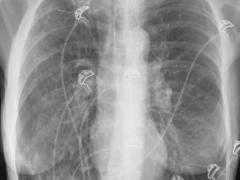

Een vrouw met acute dyspneu

‘X-thorax op de SEH nog steeds het meest efficiënt’